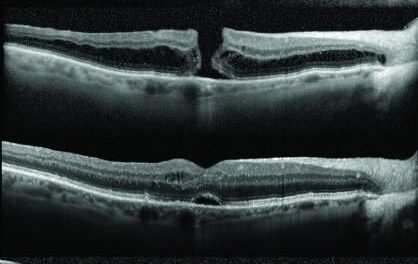

Las cataratas hace que los colores se acerquen mas a azules y grises y la DMAE deforma las imágenes, por lo que muchas veces vemos como la pintura de estos artistas y muchos más evolucionan en función de su patología.